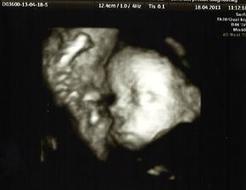

K odhalení Edwardsova syndromu v těhotenství24 slouží screening14 v 1. trimestru37, který se provádí mezi 11.16 a 13.19 týdnem těhotenství společně s případným výskytem Downova a Patauova syndromu.